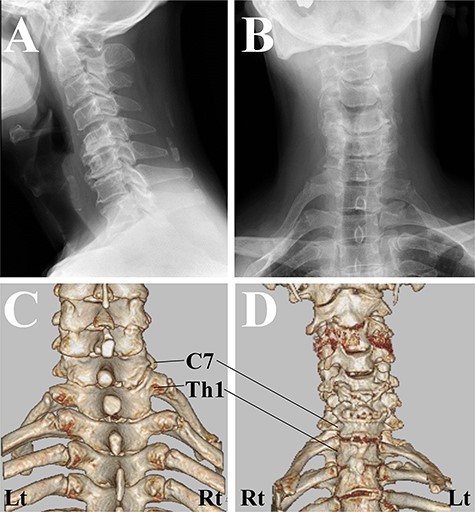

Cervical spine X-ray and computed tomography (CT) images. (A) X-rays image of lateral view showed the straight alignment of the cervical spine. (B) X-rays image of anterior–posterior view showed bilateral sloping shoulders. (C) CT image of posterior–anterior view. The first rib on the right side originated from the higher position of the Th1 vertebra than that on the left side. (D) CT image of anterior–posterior view. CT revealed the existence of the joint between the first rib and the second rib on the right side.

One year after the onset of symptoms in his left hand, he complained of weakness in his right fingers and hand (MMT grade 2) without any pain/numbness. We confirmed the pulses of the radial artery at this original presentation. Magnetic resonance imaging showed a more severe compressive lesion at the C5-C6 level from 1 year ago, while computed tomography (CT) revealed that there was a difference between the attachment to the Th1 vertebrae between the right and left first ribs, and the existence of the joint between the first rib and the second rib (Fig. 2). Given his past history and his clinical/radiological findings, the symptoms were compatible with CSA. However, 2 weeks after the right-hand paresis, his sloping shoulder, as well as weak pulse of the radial artery, pain and gangrene in his right hand gradually developed probably due to concurrent TOS (Fig. 3).